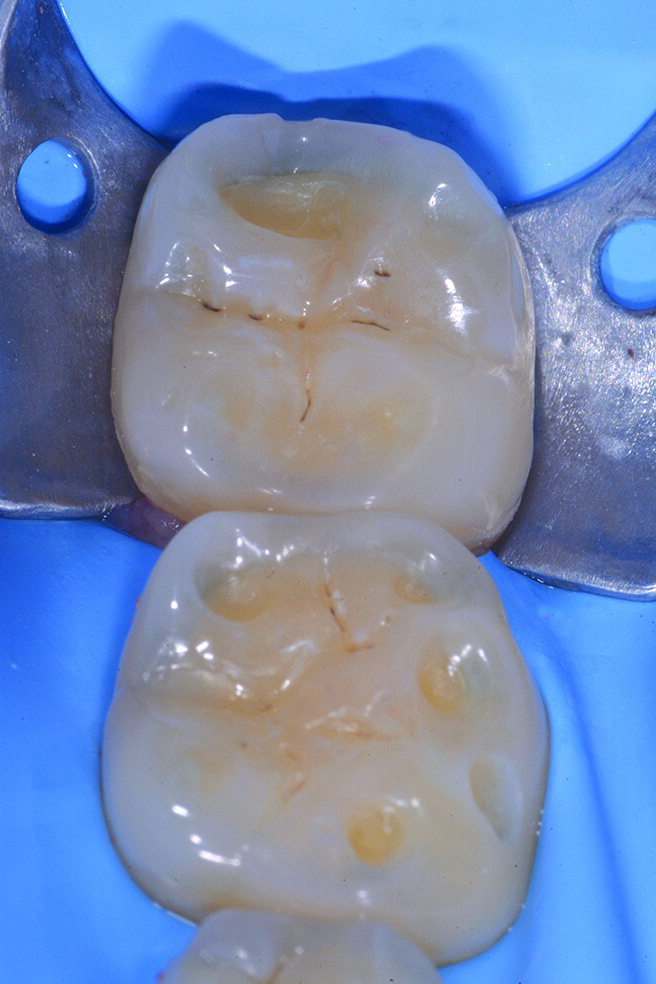

Per evitare preparazioni che porterebbero al sacrificio di tessuto sano si preferisce ricostruire gli elementi in modo ultraconservativo con una tecnica diretta per addizione. I restauri presenti su 4.6 e 4.7 vengono rimossi e tutte le superfici da ricostruire sabbiate con ossido di alluminio e lo smalto interessato all’adesione viene poi lucidato con un gommino in silicone prima delle fasi adesive. Le cavità su 4.6 e 4.7 vengono prima riempite con piccoli incrementi di dentina quindi tutte le superfici occlusali erose e/o abrase vengono ricostruite con strati sottili di smalto composito (Enamel Plus HRi Bio Function).

Figg. 2-5_Rimozione dei vecchi restauri presenti su 4.6 e 4.7: gli elementi vengono restaurati con tecnica diretta utilizzando dentina e smalto Enamel Plus HRI Bio Function.

Figg. 6-9_Le superfici occlusali erose e/o abrase vengono ricostruite con strati sottili di smalto composito Enamel Plus HRi Bio Function.